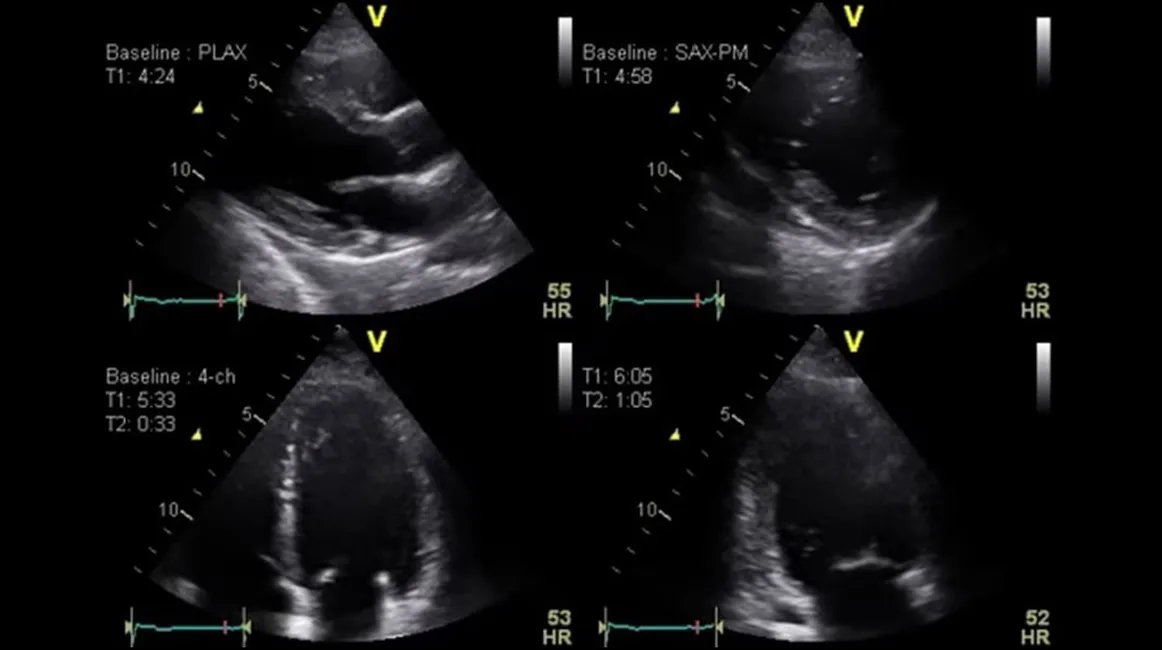

- Поддержка режима стресс-эхо и контраст-усиленной эхокардиографии (в зависимости от конфигурации), что расширяет диагностические возможности кардиологической службы.

| Специализированные кардиологические режимы | Набор режимов и инструментов для стресс-эхо, контрастных исследований и расширенных количественных оценок (при наличии соответствующих опций). |

- Кардиология: стандартная и стресс-эхокардиография, количественная оценка сократимости миокарда, мониторинг пациентов с хронической сердечной недостаточностью и пороками клапанов.